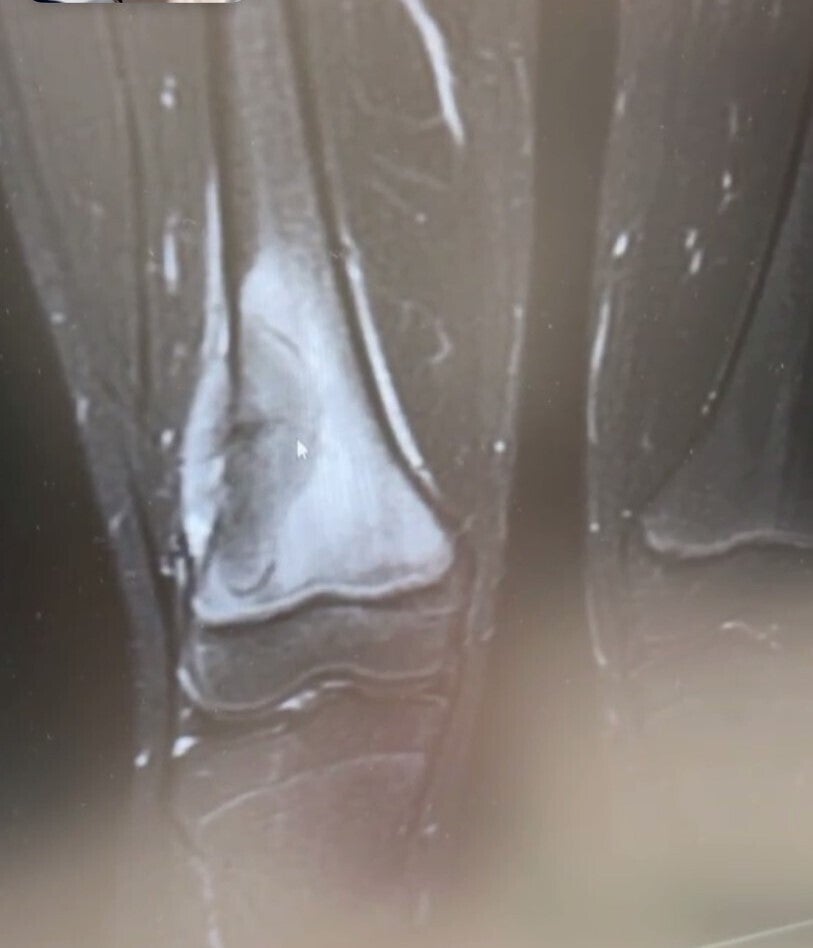

先生は念のためにレントゲンを撮りましょうとレントゲンを撮る

レントゲンの結果、先生は少し影があり

これも念のために今度は専門の病院でMRIを撮りましょうとなった

2024年12月23日 専門の病院でMRIを撮る